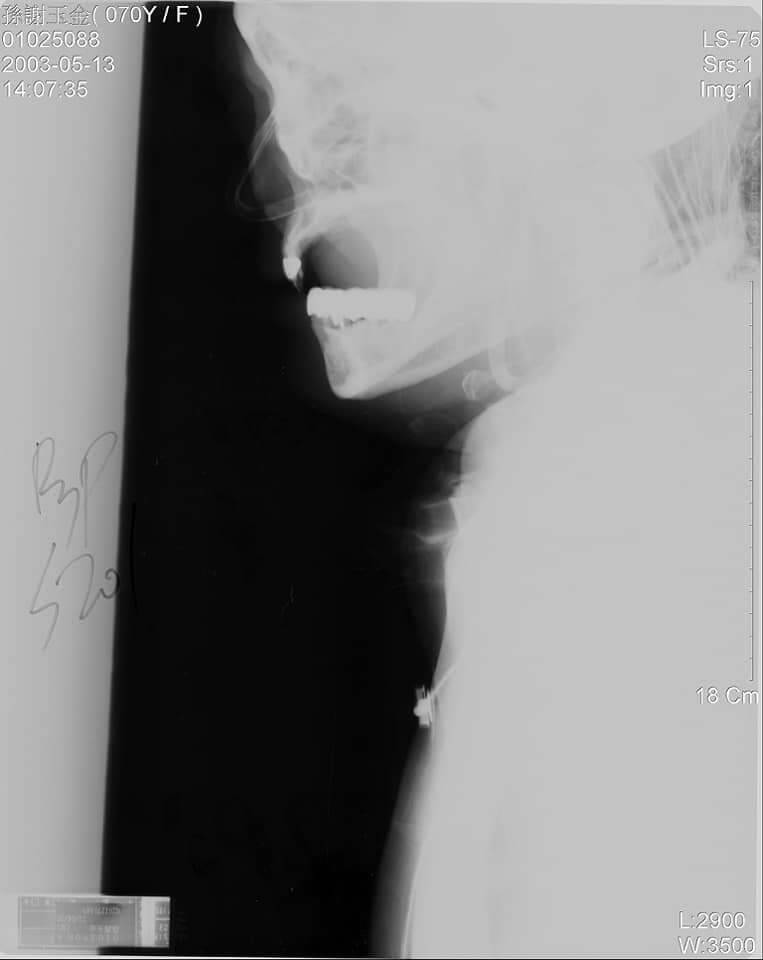

這是一張頸椎X光片,判決書謂「X光片雖有輕度曝光,惟不影響判讀者,與實情相符,應堪憑採」 該X光清清楚楚無法看到頸椎骨 東厰的大人們竟然說可以看得到,已然明顯是濫用職權、強逼當事人、社會大眾接受其不法判決。請問大家這行徑是否如東廠,且更勝東廠呢?